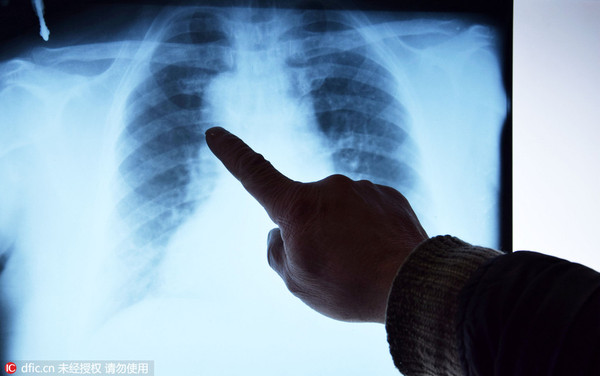

2月26日,娄底双峰村民周满英来到井字镇中心卫生院打针。让医师们意外的是,经B超和X光线检查,周女士是一位全内脏反位者。

全内脏反位(SIV)即内脏器官全部左右对称反向生长,与正常位置呈镜像分布,又称“镜面人”。是一种罕见的先天性畸形,心脏、肝脏、脾脏、胆等器官的位置与正常人相反,心脏、脾脏在右边,肝脏位于左边。除了器官位置改变之外,其生理功能基本正常,国内外关于此方面的报告很少。